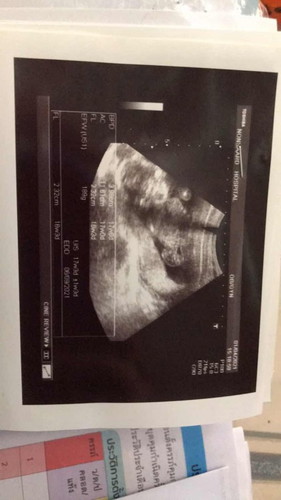

เพิ่งไปเจาะน้ำคร่ำมาวันนี้เหมือนกันค่ะ มีความเสี่ยงสูงตัวโครโมโซมคู่ที่18 ลุ้นผลมากค่ะ

ไปเจาะมาแล้วค่ะแต่ผลออกมาเสี่ยงสูงเลยต้องเจาะน้ำคร่ำ